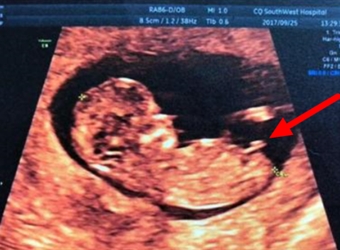

其实在做超声检查的时候,大部分医生都是看到全景的,也有医生会给孕妈一些暗示,那么NT胎儿男女医生暗示会说什么呢,NT男宝图片nub节点怎么看?更多关于生男…

NT检查是一种孕期的筛查,主要是为了判断婴儿是否有畸形概率,而NT检查的图也属于超声影像的一种,那么NT图弯着就是男孩吗,女宝宝的NT图是平躺着的吗?更多关…

在国外还是有通过超声胎儿性别的方法的,其中最简单的方式就是看宝宝的第二性征,那么NT检查图看男女看哪个角度呢,NT胎儿男女区别对照图,更多关于生男生女的…